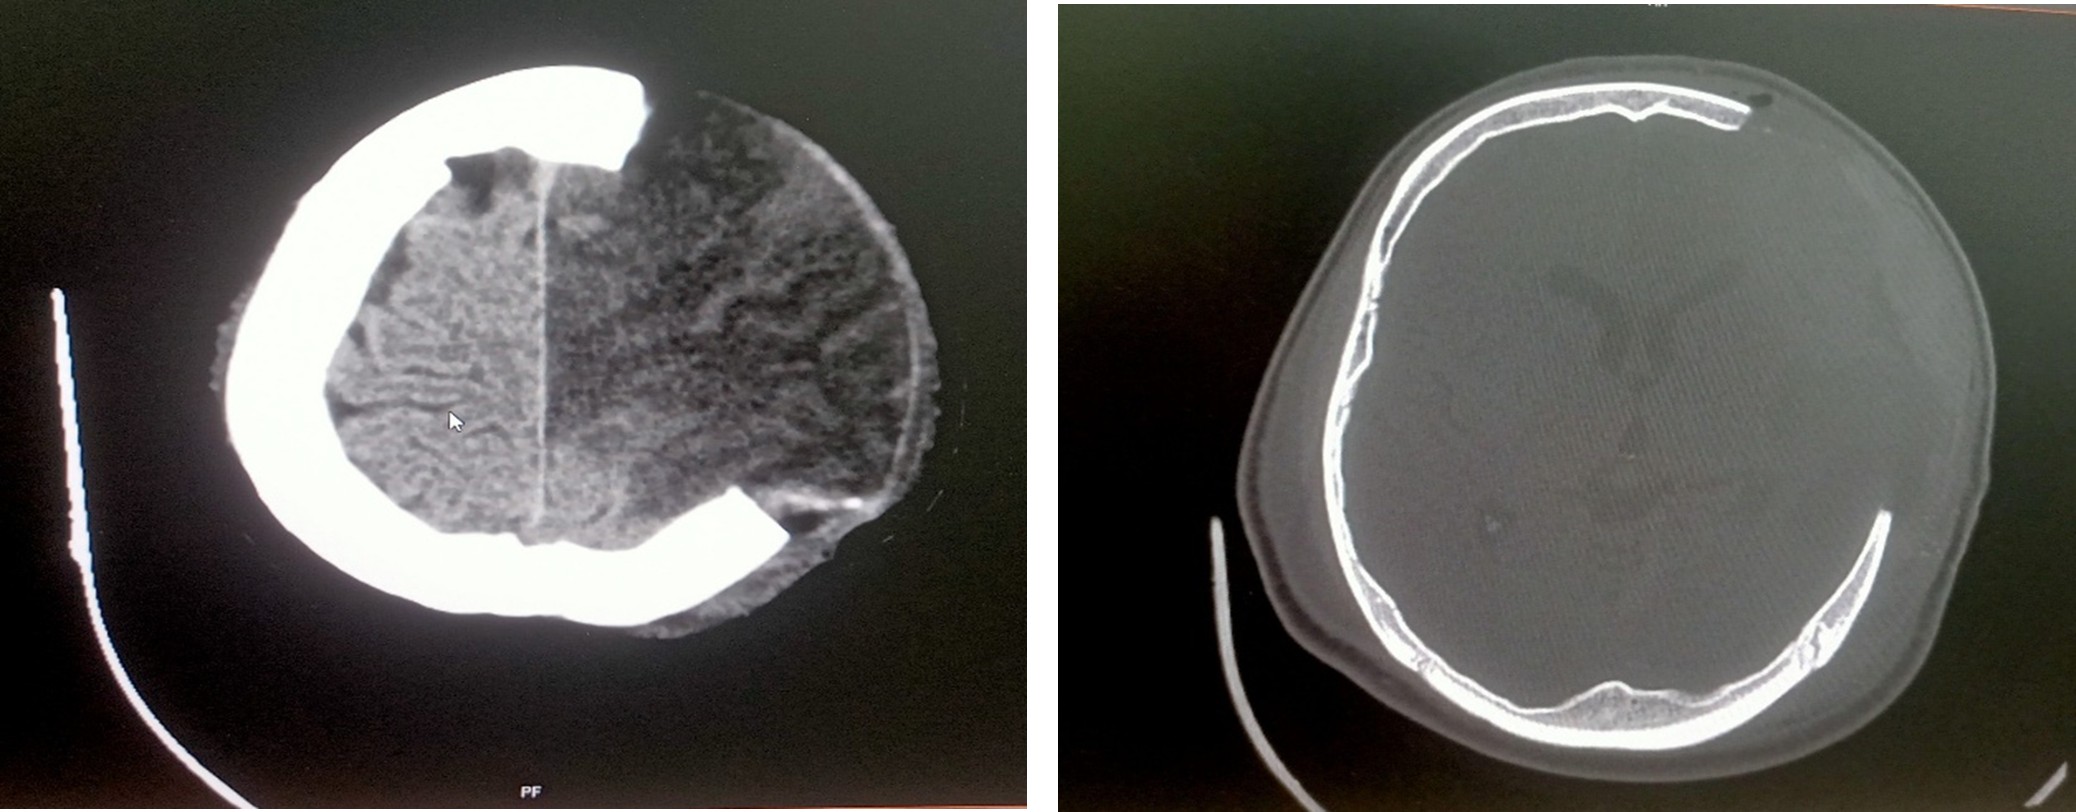

Multislice CT scan brain plain study – 23.06.2025

Postoperative bony defect left fronto – temporo – parietal region with infarct in left MCA and ACA territory with minimal mass effect

Multislice CT scan brain plain study – 24.06.2025

K/c/o Left ACA and MCA territory infarct status post craniectomy, on follow-up

Subacute infarct with hemorrhagic transformation seen in left frontal parietal and temporal lobes

Surgical Management

- Emergency Left Fronto-Parietal decompressive Craniotomy/temporal lobectomy and cisternostomy were performed because of CT brain done and revealed that new onset of ACA tertiary- Acute with midline shift and mass effect on 18/06/2025

- Malignant Middle Cerebral Artery (MCA) infarct and surgical decompression: Pre-op and post-op CT brain findings